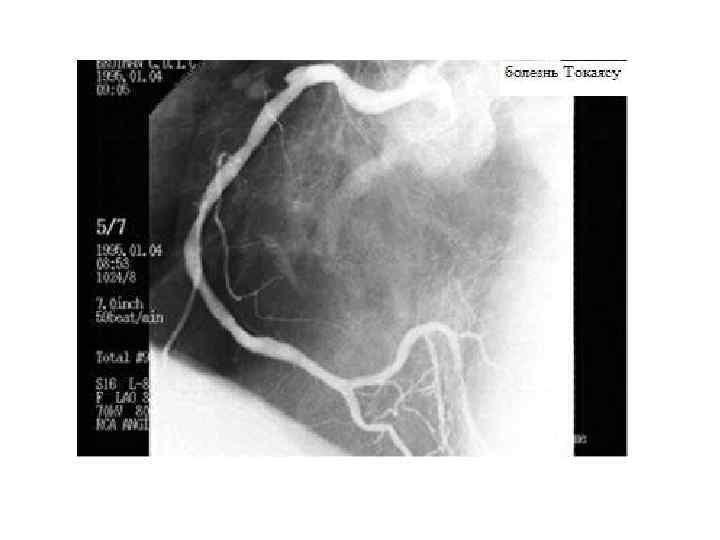

Диагностика вазоренальной АГ • При ультрасонографии и урографии – уменьшение одной почки, замедление выведения контраста. • На УЗИ – эхоскопические признаки асимметрии формы и размеров почек, превышающие 1, 5 см. • Ангиография выявляет концентрическое сужение пораженной почечной артерии. • Дуплексное УЗ-сканирование почечных артерий определяет нарушение магистрального почечного кровотока.

Данные аортографии больной М. , 24 года: множественные двусторонние стенозы почечных артерий при фибромышечной дисплазии – «жемчужное ожерелье» или «четки»